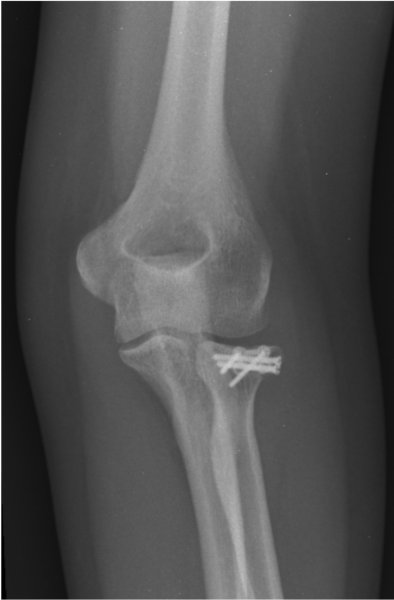

1b. X-rays after surgery, showing the fracture after fixation

A rotation of the x-ray